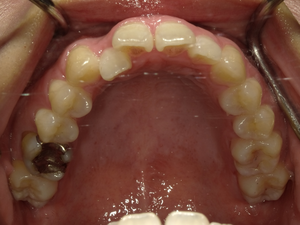

●ご相談内容:歯がガタガタしてる●矯正の種類:マウスピース型矯正「インビザライン」●治療期間:26週間●治療費用:66万円(税込)